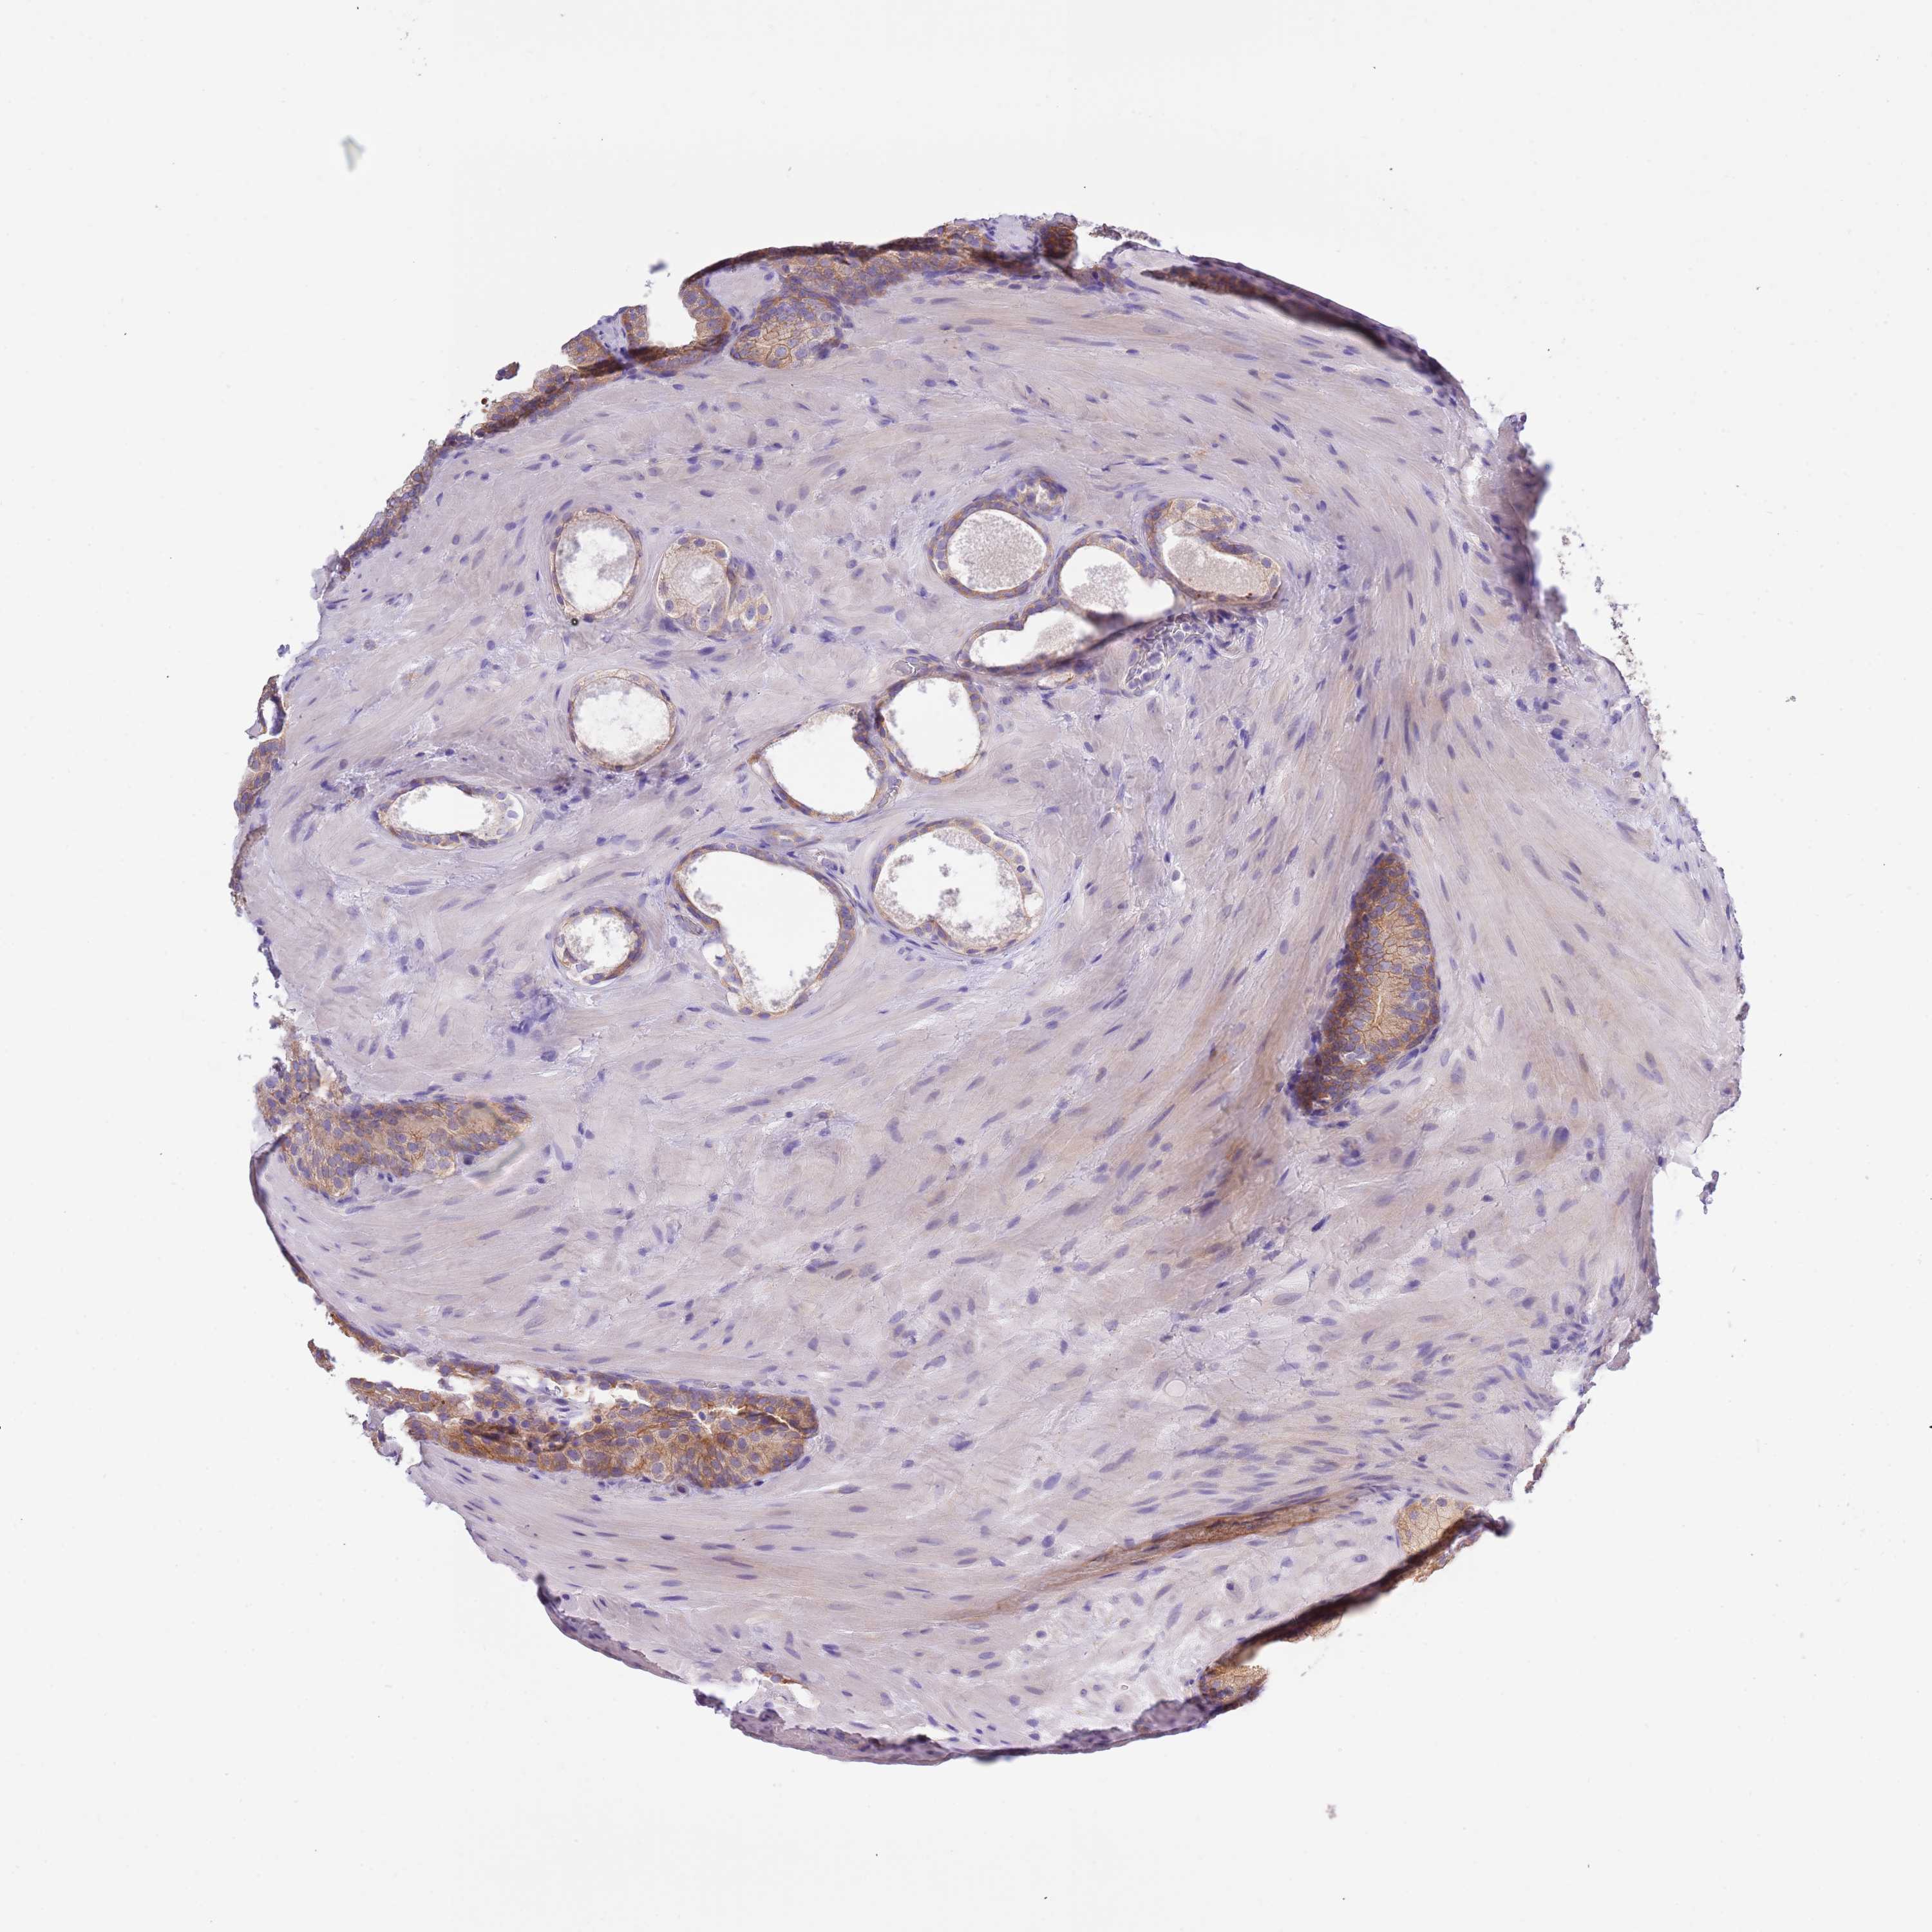

PROSTATE CANCER - Protein expressioni

A mouse-over function shows sample information and annotation data. Click on an image to view it in a full screen mode. Samples can be filtered based on level of antibody staining by selecting one or several of the following categories: high, medium, low and not detected. The assay and annotation is described here.

Antibody stainingi

Antibody staining in the annotated cell types in the current human tissue is reported as not detected, low, medium, or high, based on conventional immunohistochemistry profiling in selected tissues. This score is based on the combination of the staining intensity and fraction of stained cells.

Each image is clickable and will lead to virtual microscopy that enables deeper exploration of all samples and also displays staining intensity scores, fraction scores and subcellular localization as well as patient and tissue information for each sample.

Antibody HPA039291

Antibody HPA044062

Antibody CAB017448

Staining

High

Medium

Low

Not detected

Intensity

Strong

Moderate

Weak

Negative

Quantity

>75%

75%-25%

<25%

None

Location

Nuclear

Cytoplasmic/membranous

Cytoplasmic/membranous,nuclear

Adenocarcinoma, Low grade